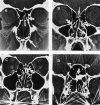

Results: Committee members agreed to adopt the term “rhinosinusitis” and reached consensus on definitions and strategies for clinical research on acute presumed bacterial rhinosinusitis, chronic rhinosinusitis without polyposis, chronic rhinosinusitis with polyposis, and classic allergic fungal rhinosinusitis. Symptom and objective criteria, measures for monitoring research progress, and use of symptom scoring tools, quality-of-life instruments, radiologic studies, and rhinoscopic assessment were outlined for each condition.